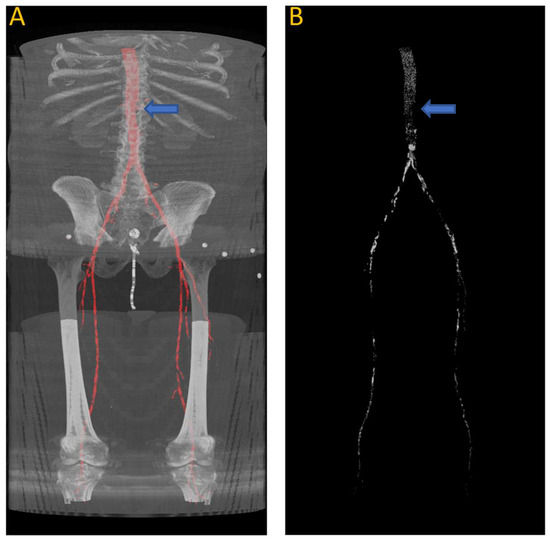

Figure 9 shows the results of the segmentation of the vascular system using the first model and calcification tracking within these arteries of the same patient analyzed in Figure 8. It is evident that this patient exhibits a high degree of arterial calcification, with a significant presence of calcified deposits. The manual calcification score on this patient is measured from slice 93 (left renal artery), indicated by the blue arrow in Figure 9, all the way to the patella. The manual calcification score is 7892, while the automatic is 7707, giving an Absolute Percentage Error (APE) score of 2.04%.

Figure 9.

(A) Automated artery segmentation. (B) Automated calcification tracking in arteries in a CT image for patient “J2” after intensity thresholding on (A). The blue arrow indicates the location of the left renal artery, which serves as the starting point for measuring the calcium score.